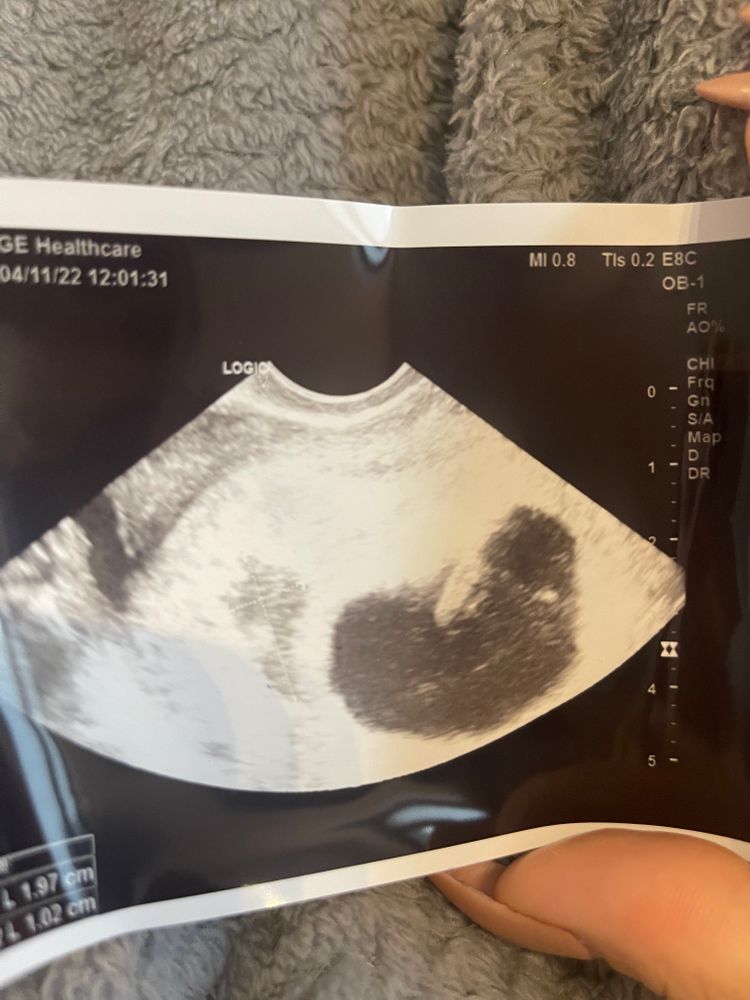

Надежда Веровна , Изображение